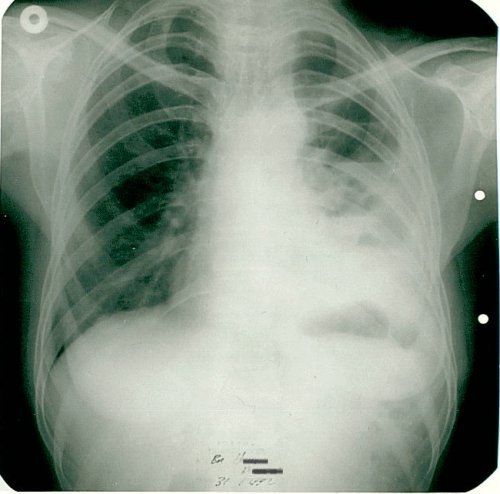

1991 yılında az diferansiye fibröz malign mezotelioma teşhisi konulan 53 yaşındaki kadın hasta, çok düşkün haldeyken immünomodülatör tedavi ile 9 ayda tam iyileşme sağladı. 2000 yılında hasta remisyondaydı ve 9 yıl boyunca hastalık belirtisi göstermedi.

Nefes darlığı, göğüs ağrısı - plevral sıvı

Ödem kayboldu, radyoloji normale yakın

Tetkiklerde sol plevra boşluğunda sıvı saptandı.

Torakoskopi ve Coparvacs uygulamasına rağmen akciğerde tam ekspansiyon sağlanamadı.

Ödem kaybolmuştu, dispne ve taşikardi düzelmişti. İki ay daha aynı tedaviye devam edildi.

Radyolojik bulgular normale yakın hale gelmişti ve immünomodülatör tedaviyi kesmesi önerildi.